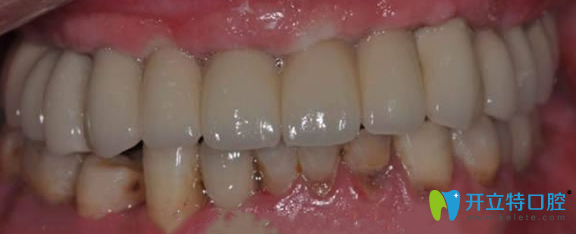

金臺(tái)口腔半口牙缺失術(shù)后效果圖:

南京金臺(tái)口腔門(mén)診讓張叔擁有了整齊的牙齒,見(jiàn)人就夸金臺(tái)口腔田忠奎院長(zhǎng)不光種植牙技術(shù)好,牙齒矯正方面在南京地區(qū)也是赫赫有名。還建議大家一定要到正規(guī)的口腔進(jìn)行口腔診治,說(shuō)的有模有樣的,被樓下的阿姨稱為“民間牙醫(yī)”。